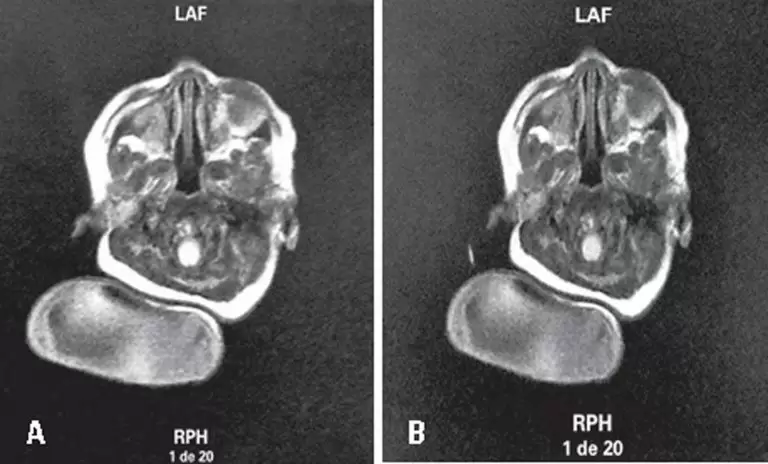

Mielocele occipital congênita

A encefalocele congênita é um defeito do fechamento do tubo neural, ocorrendo herniação de conteúdos cranianos devido à malformação congênita do crânio, sendo sua forma mais comum a occipital.() A encefalocele geralmente ocorre por um defeito no osso occipital na quarta semana da embriogênese e pode se estender para o forame magno, envolvendo o arco posterior do atlas.() O conteúdo do saco herniário varia, sendo de pior prognóstico aquele com maior conteúdo craniano em seu interior.(,) A etiologia desta malformação engloba fatores genéticos e ambientais, como deficit de folato, cuja prevenção é realizada com o uso de ácido fólico durante o período pré-concepcional até 12 semanas de gestação e a má assistência ao pré-natal.(,) Embora varie nas diversas regiões demográficas, a incidência dos defeitos do fechamento do tubo neural situa-se em torno de 1:1.000 nascidos vivos.(,)

Tanto uma assistência pré-natal adequada, quanto a realização de exames de imagem são importantes para identificar variações que orientam a conduta desta afecção – daí a importância da descrição do caso clínico e suas imagens de encefalocele.